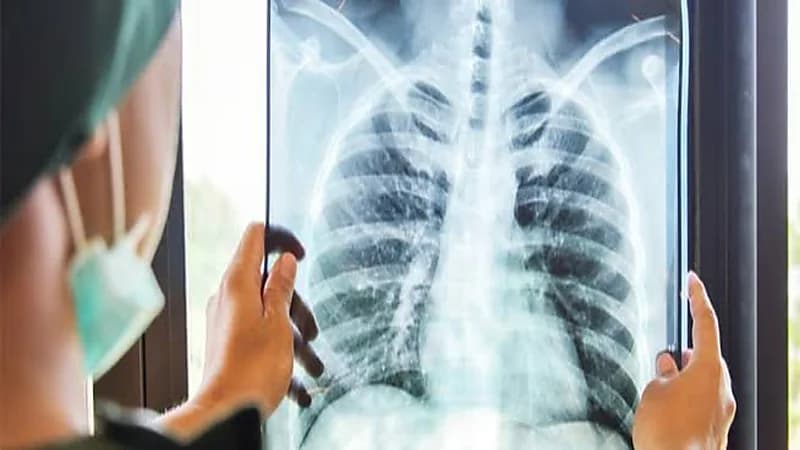

أوضح الدكتور عادل باعيسى، أنه يُعرف السل أو "الدرن" بأنه مرض معدٍ يُصاب به الشخص نتيجة العدوى ببكتيريا تسمى المايكوبكتيريوم، والتي تهاجم الرئتين، وقد تصيب أجزاء أخرى بالجسم منها الكلى، الدماغ، والحبل الشوكي.

وتتمثل الأعراض في: السعال لمدة ثلاثة أو أربعة أسابيع، السعال المصحوب بدم أو مخاط، ألم الصدر، أو ألم أثناء التنفس أو السعال، فقدان الوزن غير المقصود، الإرهاق، الحُمّى، التعرّق الليلي، القشعريرة، فقدان الشهية، بينما ينتج داء السل عن بكتيريا تنتقل من شخص لآخر عن طريق الهواء.